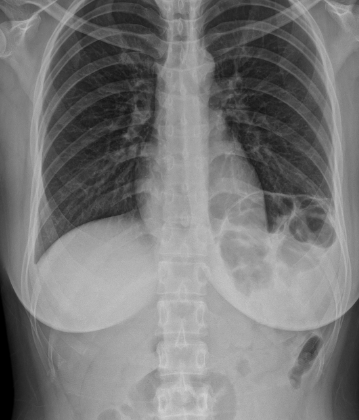

탈장이란 신체의 장기가 제자리에 있지 않고 다른 조직을 통해 돌출되거나 빠져나오는 증상을 말합니다. 신체 어느 곳에나 생길 수 있지만 대부분의 탈장은 복벽, 즉 배 안의 앞쪽의 벽에서 발생하는데, 복벽 탈장은 복강을 둘러싼 근육과 근막 사이에 복막이 주머니 모양으로 돌출되어 비정상적인 형태를 이루는 상태입니다. 주머니 속에 복강 내 장기가 포함되기도 한다. 탈장은 생긴 부위에 따라 여러 가지로 분류되기도 합니다.

가장 흔한 형태로는 사타구니 부위에 생기는 서혜부 탈장, 그리고 그 외에 대퇴와 아랫배가 만나는 부위의 대퇴 탈장, 수술 상처 부위에 생기는 반흔 탈장, 배꼽 부위의 약해진 부분을 통해 발생하는 제대 탈장 등이 있다.